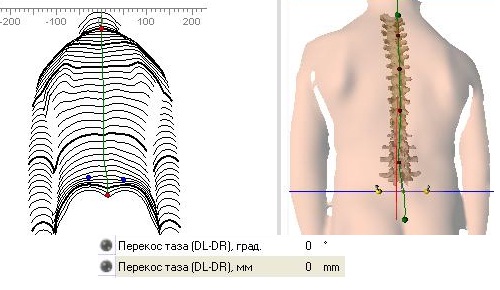

Оптическая диагностика позвоночника Diers: изображения и технологии

Раздел: Мир в картинках